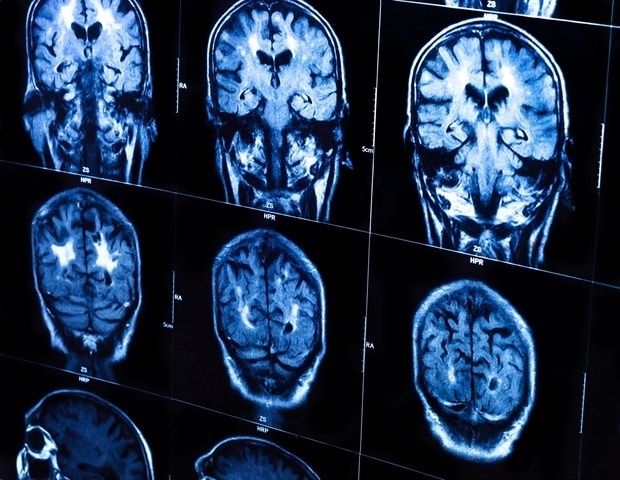

Healthy blood vessels matter for more than just heart health. Vascular well-being is critical for brain health and potentially in addressing age-related cognitive decline and neurodegenerative disorders, like Alzheimer’s disease, according to new study led by Penn State researchers. The findings point to an understudied but possible key role the brain’s vascular network -; or energy infrastructure -; plays in the onset of neurodegenerative disease.